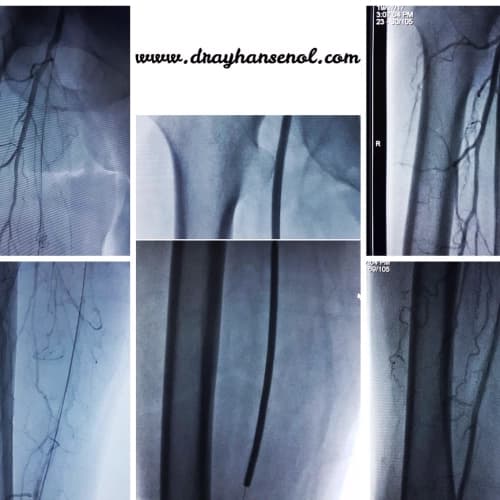

Böbrek damar darlığında stentleme, Görüntüleme eşliğinde biyopsiler(tiroid, prostat, karaciğer, akciğer, böbrek), Böbrek Atardamarı Tıkanıklığı (Renal Arter Trombozu)devamı